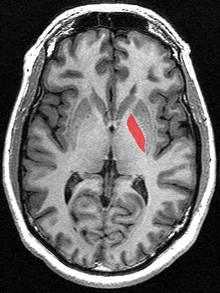

Horizontal slice of MRI-image showing the globus pallidus.- Globus pallidus